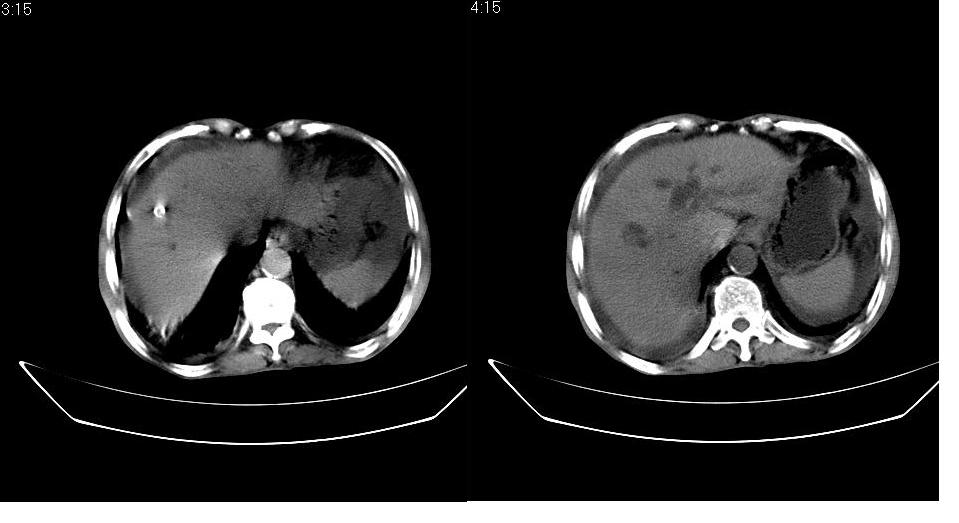

男 78岁,全身黄染,病人家属拒绝增强。

胆总管下端梗阻(原因待查)伴肝内外胆管扩张、胆囊积水。

肝周 脾周 胆囊窝内明显积液,胆囊扩大,胆囊壁模糊,肝内胆管扩张。考虑;胆囊癌周边侵润伴腹水。

周 脾周 胆囊窝内明显积液,胆囊扩大,胆囊壁模糊,肝内胆管扩张。考虑;胆囊癌周边侵润伴腹水。

1、梗阻性黄疸(胆总管下段病变或十二指肠病变)。

2、胆囊炎,腹水。